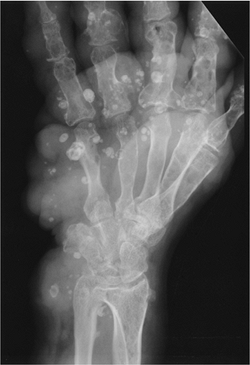

![]() |

FIGURE 15-18 Maffucci syndrome. Oblique radiograph showing multiple enchondromas and soft tissue masses with vascular calcifications.